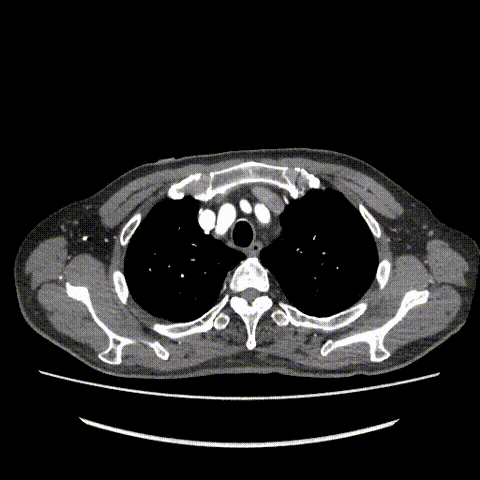

术前CTA:主动脉弓、左锁骨下动脉、胸主动脉附壁血栓伴部分穿透性溃疡。病变位于左锁骨下动脉根部前壁位置,近端锚定区不足

术前CTA横截面